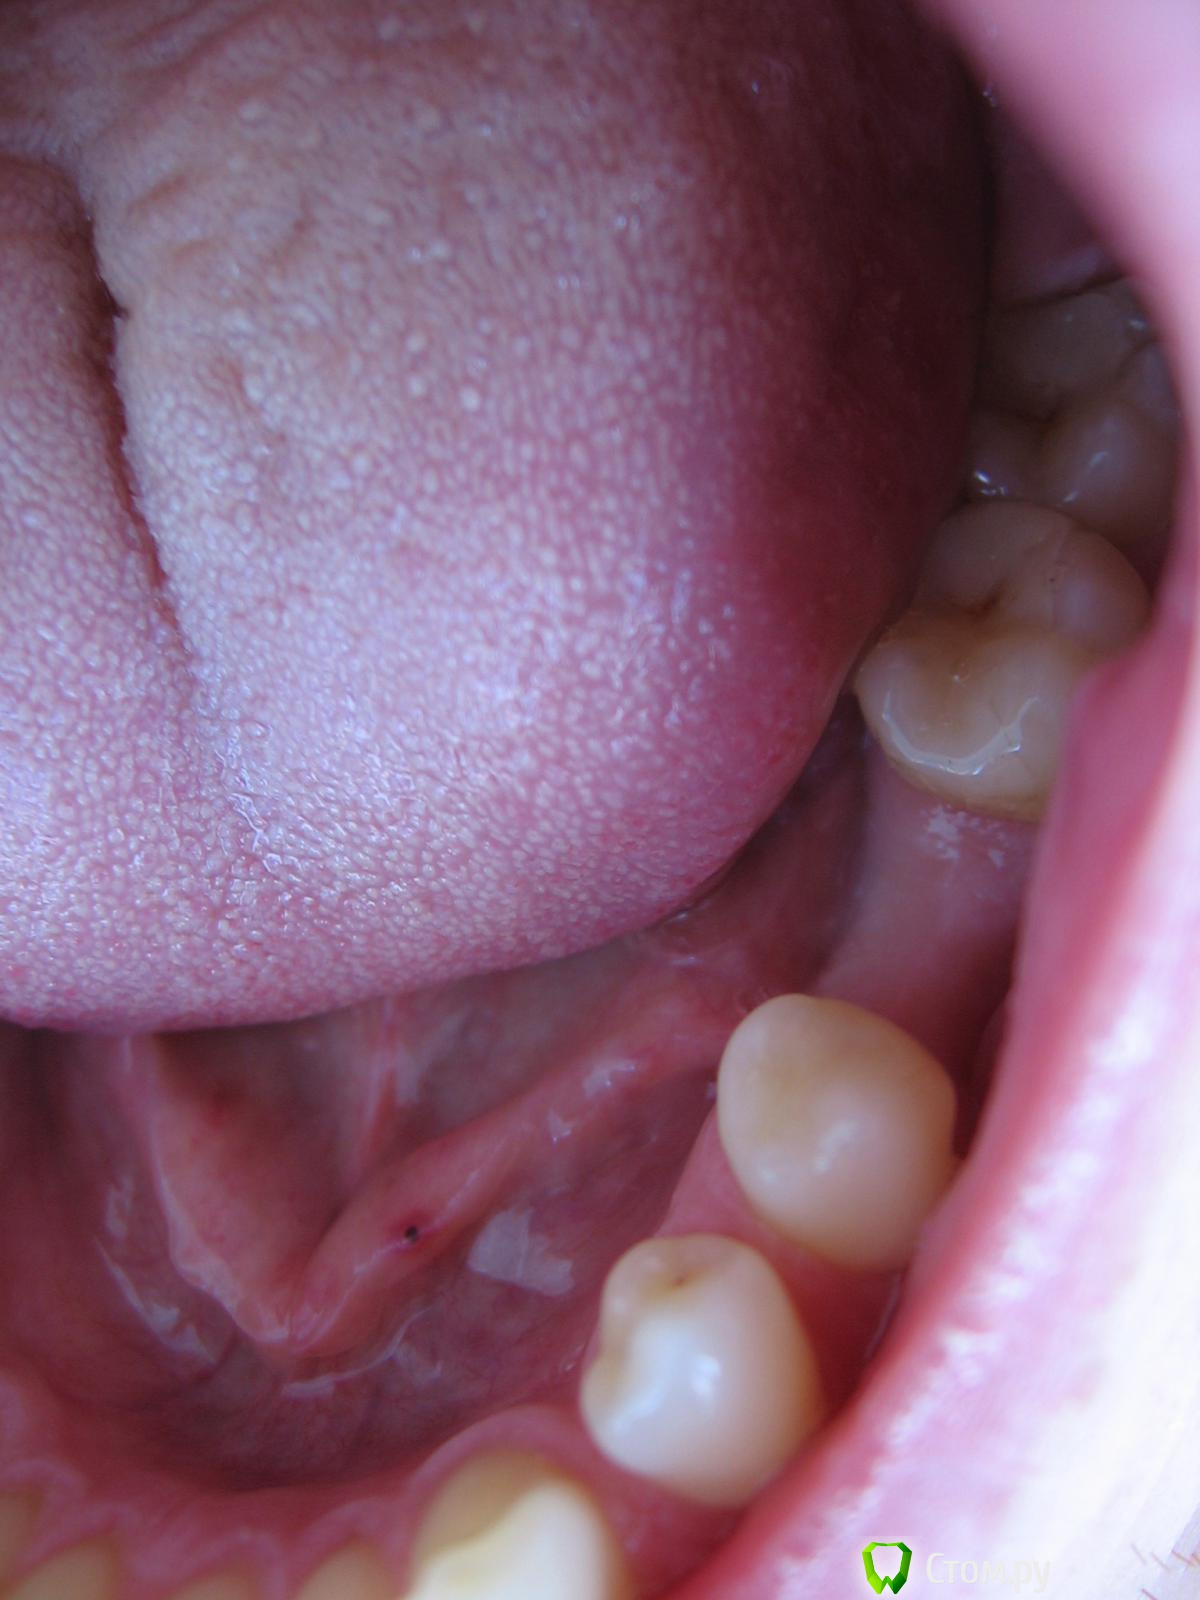

bobrdobr Опубликовано 7 февраля, 2014 Автор Поделиться Опубликовано 7 февраля, 2014 Про пластику понял. Фото - без проблем. Изловчился сделать такие. КТ могу сделать, если она необходима. Ссылка на комментарий

IvanK Опубликовано 7 февраля, 2014 Поделиться Опубликовано 7 февраля, 2014 фото не информативны. как минимум, увеличить объем десны придется. Ссылка на комментарий